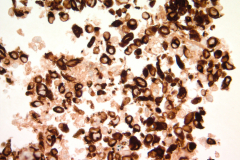

Specimen Type: FNA of RUL nodule. ThinPrep® Non-Gyn and conventional smears with Diff Quik stain, H&E stain (traditional cell block), Papanicolaou stain and AE1/AE3 (traditional cell block).

IHC: AE1/AE3, EMA and ERG – positive, CD34 – negative and loss of INI 1 expression.